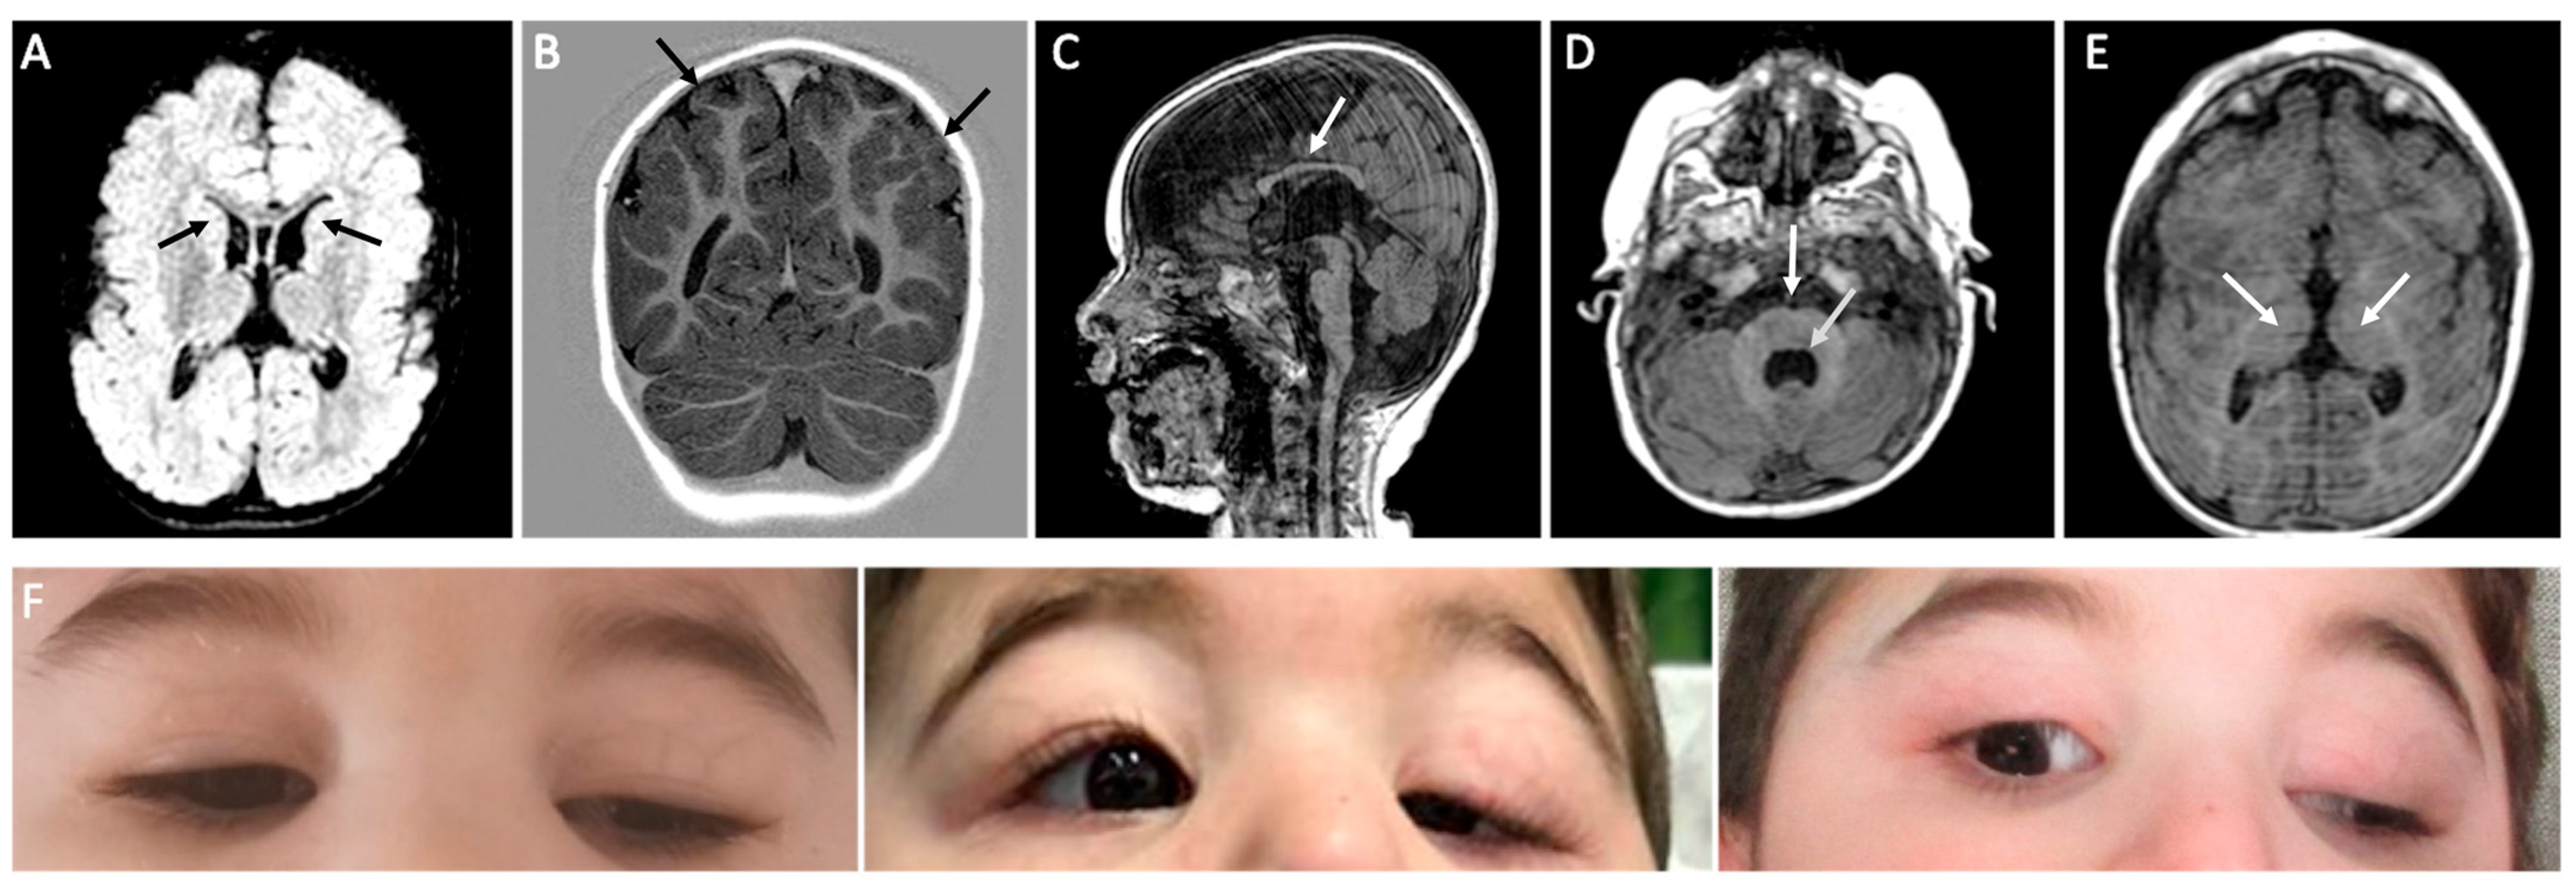

3.1. Clinical Findings

3.2. Molecular Findings and Structural Analysis